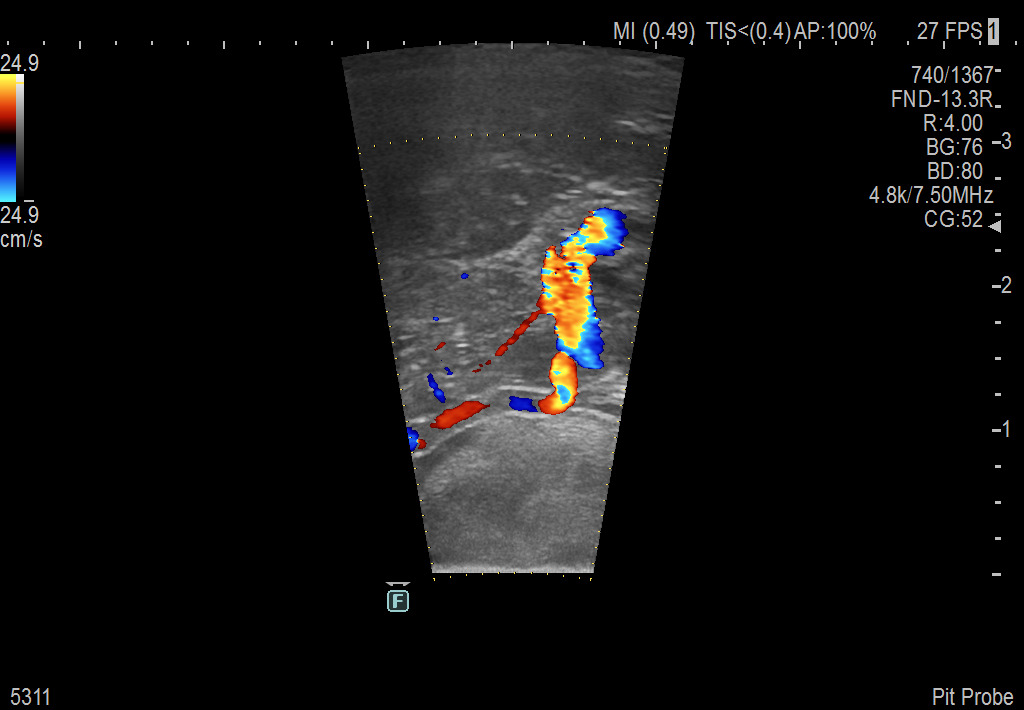

Pituitary Procedure using UST-5311

Exclusive 10mm side-fire linear array transducer with 2.87mm diameter is ideal for real-time visualization through and behind structures and instant, scalable definition of anatomy and vascularity including the ability to delineate and define tumor margins.